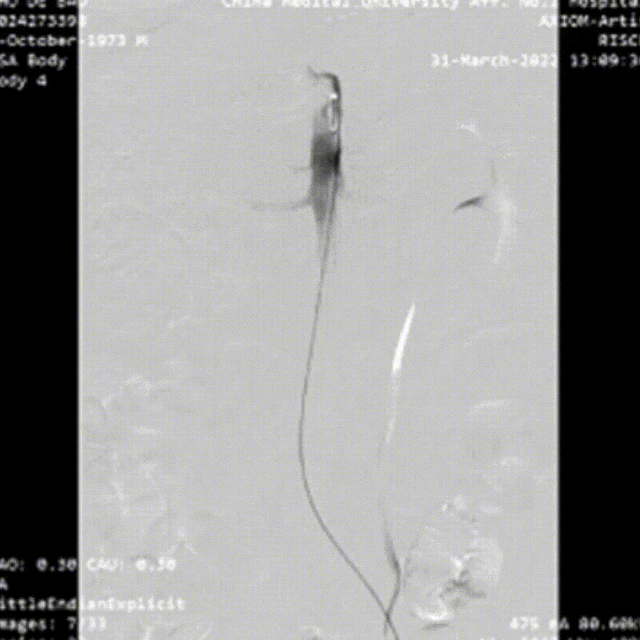

34岁男性,SMI灌注不良,TEVAR后SMA重建

SMA缺血无改善:SMA重建、支架置入。肠坏死时考虑开腹或腔镜手术。